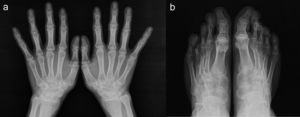

Reporte de casoPaciente varón de 17 años de edad; a los 13 años presentó dolor de cadera derecha y de rodilla izquierda. Cinco meses más tarde presentó inflamación de ambas rodillas y de interfalángicas de la mano derecha. El paciente refirió historia de dificultad al caminar desde los 3 años de edad. El examen físico mostró un adolescente con marcha anormal, escoliosis espinal y cifosis de la columna torácica. La movilidad de la columna lumbar, coxofemorales, rodillas, tobillos e interfalángicas de la mano derecha estaba severamente limitada. Las radiografías de manos y pies (fig. 1a y b), caderas y rodillas (fig. 2a y b) revelaron osteopenia difusa, ensanchamiento tubular de las epífisis y pérdida del espacio articular, sin lesiones erosivas; las radiografías de cadera y rodillas mostraron además cambios degenerativos, con cabezas femorales ensanchadas. Las vértebras torácicas y lumbares, con vértebras aplanadas e irregularidades en las mesetas vertebrales (fig. 3a y b). La proteína C reactiva y la velocidad de sedimentación globular eran normales.

La DPSR simula clínicamente una artritis idiopática juvenil en etapas tempranas1,2; sin embargo, las evidencias que establecen el diagnóstico de esta displasia ósea son la afectación articular no inflamatoria y los hallazgos radiológicos característicos, como la presencia de epífisis ensanchadas, osteoporosis generalizada y platispondilia3.